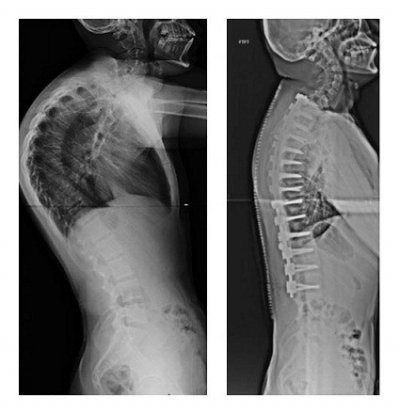

Хирургическое лечение горбатой спины требуется при превышении кривизны дуги 75 градусов или же у детей с врожденным кифозом. Операция может устранить горб и скорректировать внешний вид спины, помочь облегчить боль, но она сопряжена с довольно высоким риском осложнений, которые часто превалируют над потенциальной пользой.

Результат хирургического лечения горба на спине

Для лечения кифоза обычно используется метод спинального слияния. Это связано с объединением позвонков, ответственных за кривую позвоночника.

Как это происходит? Хирург делает разрез на спине, в позвонки устанавливается система креплений и крючков. С их помощью закрепляются специальные металлические стержни, которые удерживают хребет в нужном положении. Укрепление грудного отдела происходит с помощью костных трансплантатов, которые могут быть взяты из других костей самого пациента (например, костей таза).

При другой методике хирург может произвести удаление некоторых задних участков позвонков, чтобы изменить их наклон и уменьшить дугу в грудном отделе.

Процедура занимает от четырех до восьми часов и проводится под общей анестезией. Восстановительный период длительный (месяц–полтора) и болезненный. Около девяти месяцев нужно будет носить специальную систему, поддерживающую позвоночник, пока он полностью заживет. Вернуться к активной жизни и занятиям спортом можно будет через год после операции.